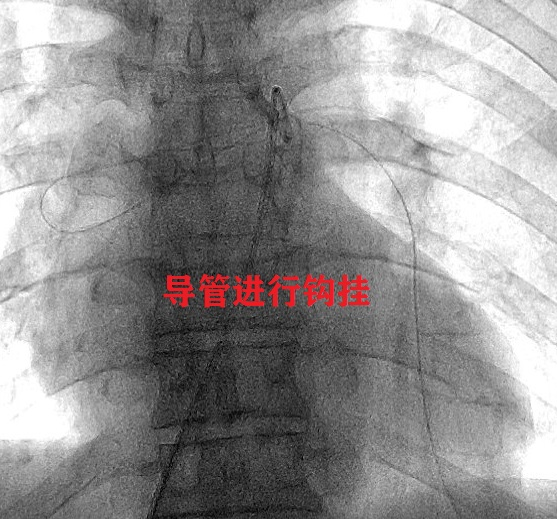

由于该导管两头均在血管分支远端,无法单纯利用圈套器进行套取。针对这一手术难点,介入医生选择在X线透视下,利用造影导管对异物进行反复钩挂。经过1个多小时的努力,终于将异物一端从上肺静脉内挑拨到了肺动脉主干内,并利用圈套器成功取出了全部脱落的长约50cm的PICC导管,取出后造影未发现明显血管损伤,目前患者状态稳定。